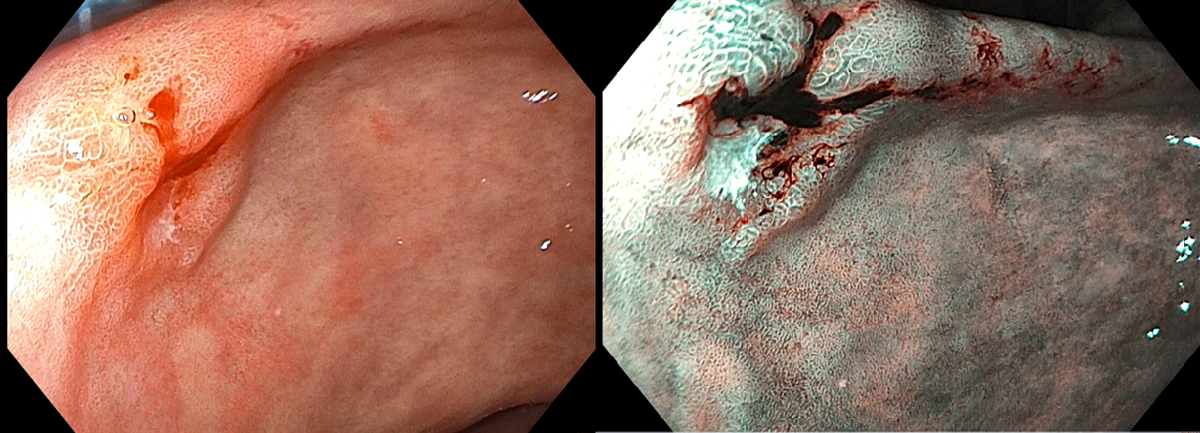

78 Chinese EGD for for dyspepsia- 1.5-cm nonulcerated depressed lesion with slightly elevated component (Paris 0-IIc+IIa) at the incisura angularis of the stomach [figure: the lesion on white light (WL) and narrow band imaging (NBI)]. Biopsy of this lesion revealed intramucosal adenocarcinoma with minute focus of poorly differentiated malignant neoplasm arising in a background of gastric mucosa with high-grade dysplasia and intestinal metaplasia (incomplete and complete types). Gastric mapping biopsy for immunohistochemical staining for H. pylori is negative. CT scan abdomen and pelvis with contrast shows no evidence of lymph nodes or distal metastasis. What is the most appropriate next step in management?

lesion is early gastric cancer (EGC)

• fulfills absolute criteria (clinical T1a intramucosal cancer, undifferentiated, nonulcerated, mucosal lesions that are ≤2 cm in size) for endoscopic submucosal dissection (ESD) (Table).

• Endoscopic resection is recommended with EGCs w negligible risk of lymph node metastasis.

• Lesions are considered absolute indications for endoscopic therapy if they are presupposed to have a <1% risk of lymph node metastasis and long-term outcomes similar to those with surgical gastrectomy.

• Endoscopic submucosal dissection TOC for EGCs

• EMR is an acceptable option for lesions smaller than 10-15mm with a very low probability of advanced histology (Paris 0-IIa).

• No RCTs with EMR vs ESD in stomach

• meta-analyses-ESD is associated with higher

• en bloc resection rates and

• histologically complete resection rates, and

• lower recurrence frequency.

• Endoscopic full thickness resection has a variable en bloc resection rate and is not a standard treatment for EGCs